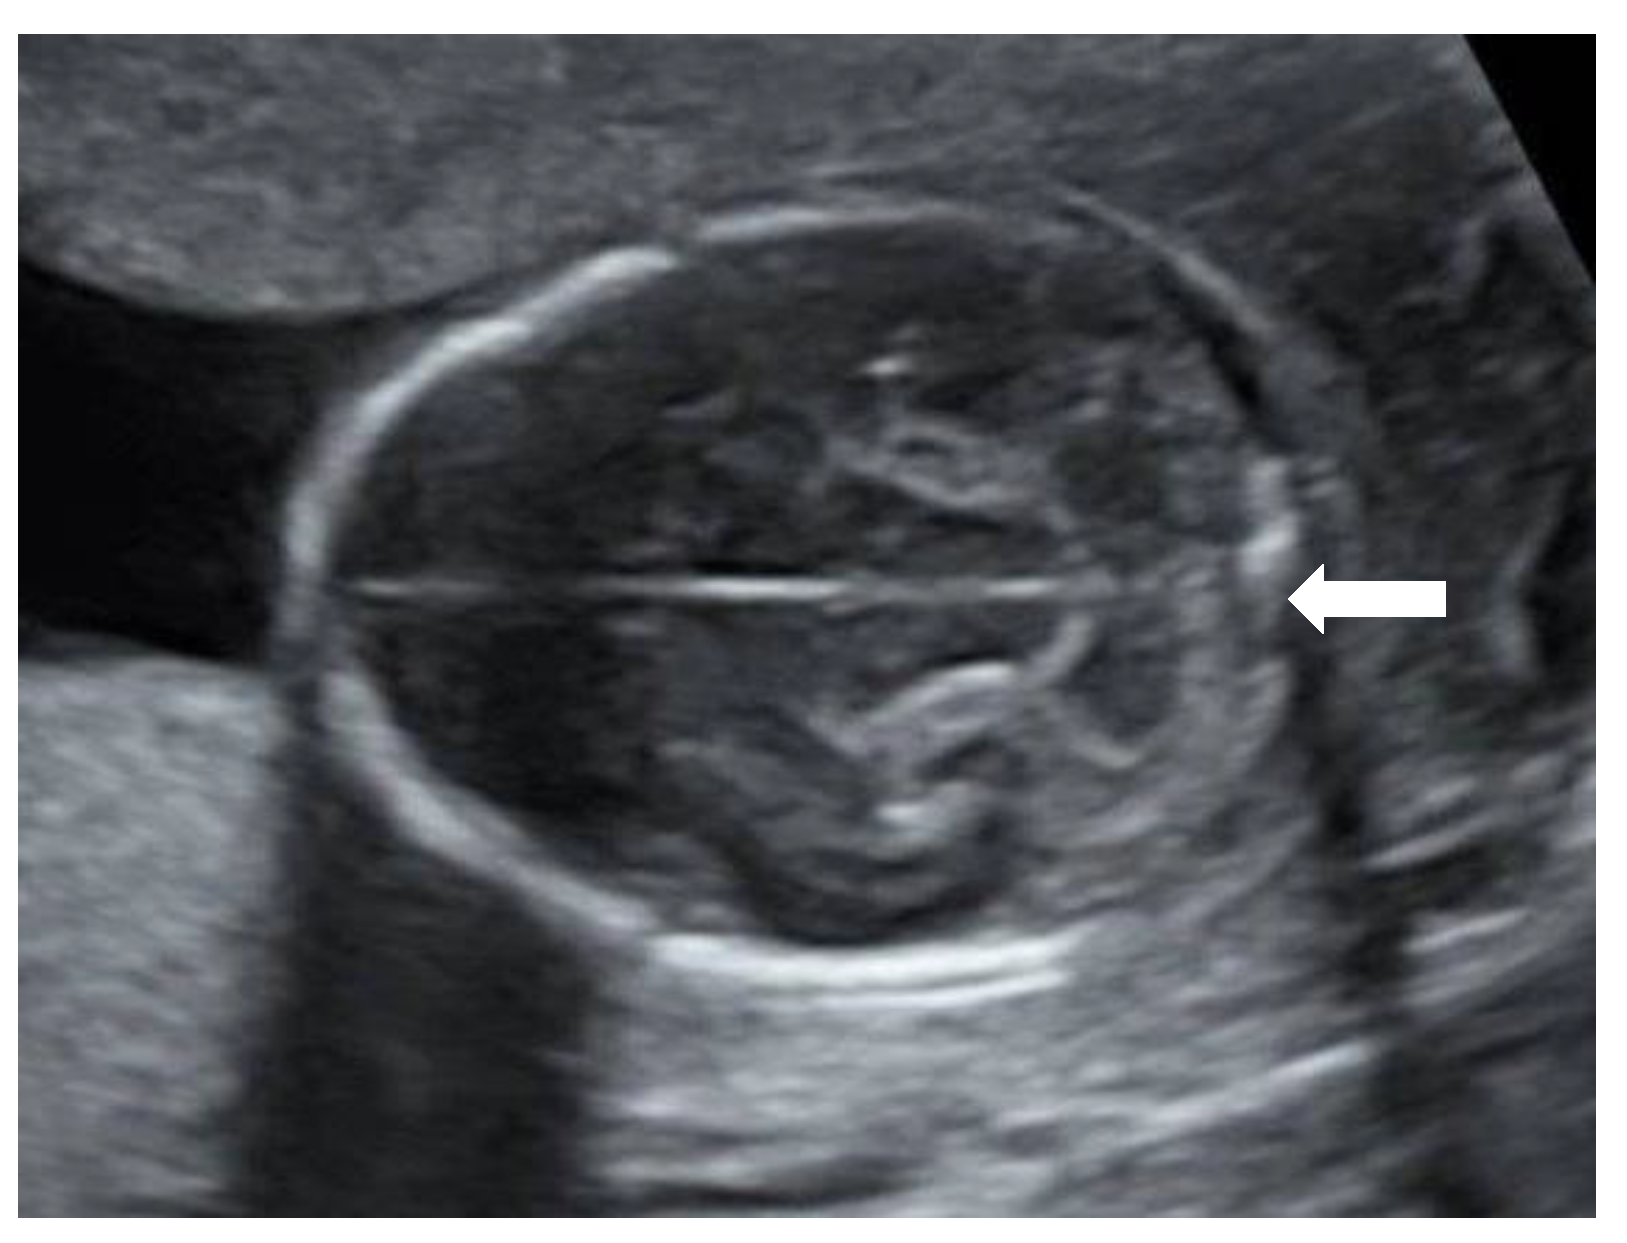

A 27-year-old primigravida was referred to the outpatient clinic of our hospital at a gestational age (GA) of 17 + 3 weeks following detection of a fetal unilateral hydronephrosis by the peripheral gynecologist. Ultrasonography demonstrated a duplex collecting system in the left kidney with hydronephrosis of the cranial pole, moderate dilatation of the upper pole ureter, and mild dilatation of the lower pole ureter. The cerebellum at that time showed a minimal posterior curving (

Figure 1), but no distinct banana-sign. Inspection of the spine was inconspicuous. The patient was reevaluated in our center at 24 weeks GA. The hydronephrosis of the upper pole of the left kidney remained stable. However, the cerebellum presented a banana-shape with herniation of the hindbrain onto C2 and minimal lemon-sign of the skull (

Figure 2). The lateral ventricles were not dilated. Ultrasound examination of the spine revealed a closed skin except for a minimal fistula in the sacro-coccygeal region (

Figure 3,

Figure 4 and

Figure 5). Furthermore, an abnormal gap between the second and third digit was seen on both hands as well as a syndactyly between the first and second toe. Cardiac sonography was normal at both 17- and 24-weeks GA, with a normal four-chamber view, outflow tracts, and three-vessel view. An amniocentesis was performed to rule out genetic anomalies and to measure alfa 1-fetoprotein. Additionally, a fetal MRI was carried out mainly to assess the fetal spine, as the cerebral findings all indicated the presence of an open neural tube defect. MRI analysis confirmed the hydroureteronephrosis as well as the lemon-shaped skull, Arnold–Chiari malformation 11mm below the foramen magnum, absent cerebrospinal fluid around the cerebellum, and possible mild tethering of the cord. However, MRI failed to demonstrate an open spina bifida or any skin defects. The Alfa 1-fetoprotein was elevated, further reinforcing the assumption of a classic spina bifida. QF-PCR showed no aneuploidy for chromosomes 13, 18, 21, X, or Y, but SNP array demonstrated a terminal multiplication of approximately 56 Mb of the long arm (3q23qter) of chromosome 3: arr 3q23q29(141903905-197845233)x2~4. The nature of the multiplication could not be deduced. Interphase FISH with probes in chromosomal regions 3q26 and 3q27 showed 4 copies of both chromosomal bands in approximately 50% of the interphases. Metaphase FISH proved that the 2 extra copies were located on a marker chromosome. Chromosomal examination of the parents showed no anomalies, demonstrating that the aberration occurred de novo in the fetus. Note, a genome-wide NIPT analysis on a blood sample taken at 27 weeks GA failed to detect this anomaly despite its size, indicating this to be a true fetal mosaicism of type 5 (TFM5).

9]. The diagnoses can be made in subtle cases, such as this one, by identifying a lower position of the conus medullaris. On the other hand, it is a difficult examination that is not suitable for routine screening but can help if suspicion is raised. Dorsal dermal sinuses are even more difficult to diagnose, as there is no presence of a cyst or mass. In these cases, the nerves and spinal cord are not usually affected and, therefore, in contrast to open lesions, this disease has a minimal functional impact. To our knowledge, this is the first case of closed spina bifida with a dorsal dermal sinus that is accompanied by secondary cranial abnormalities that has been diagnosed prenatally. In this fetus, a severe hindbrain herniation was detected while prenatal imaging demonstrated an intact spine and skin, both on MRI and ultrasound. Only by means of expert ultrasound, after increased suspicion of the diagnosis of spina bifida due to the elevated alfa 1-fetoprotein, could we find a small fistula between the skin and the spinal canal.